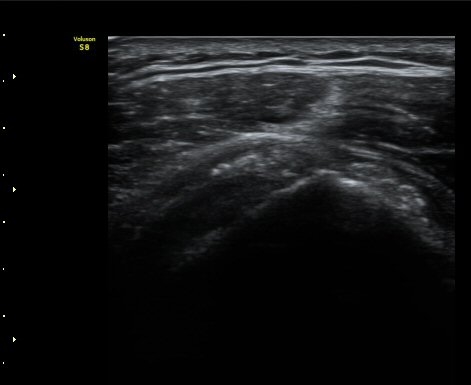

ȸÀü±Ù°³°£°Ý(rotator cuff interval) Ⱦ´Ü¸é°Ë»ç¿¡¼­ Á¡¾×³¶¸Å ¼ö¾× Àú·ù°¡ °üÂûµÈ´Ù(±×¸² 1).